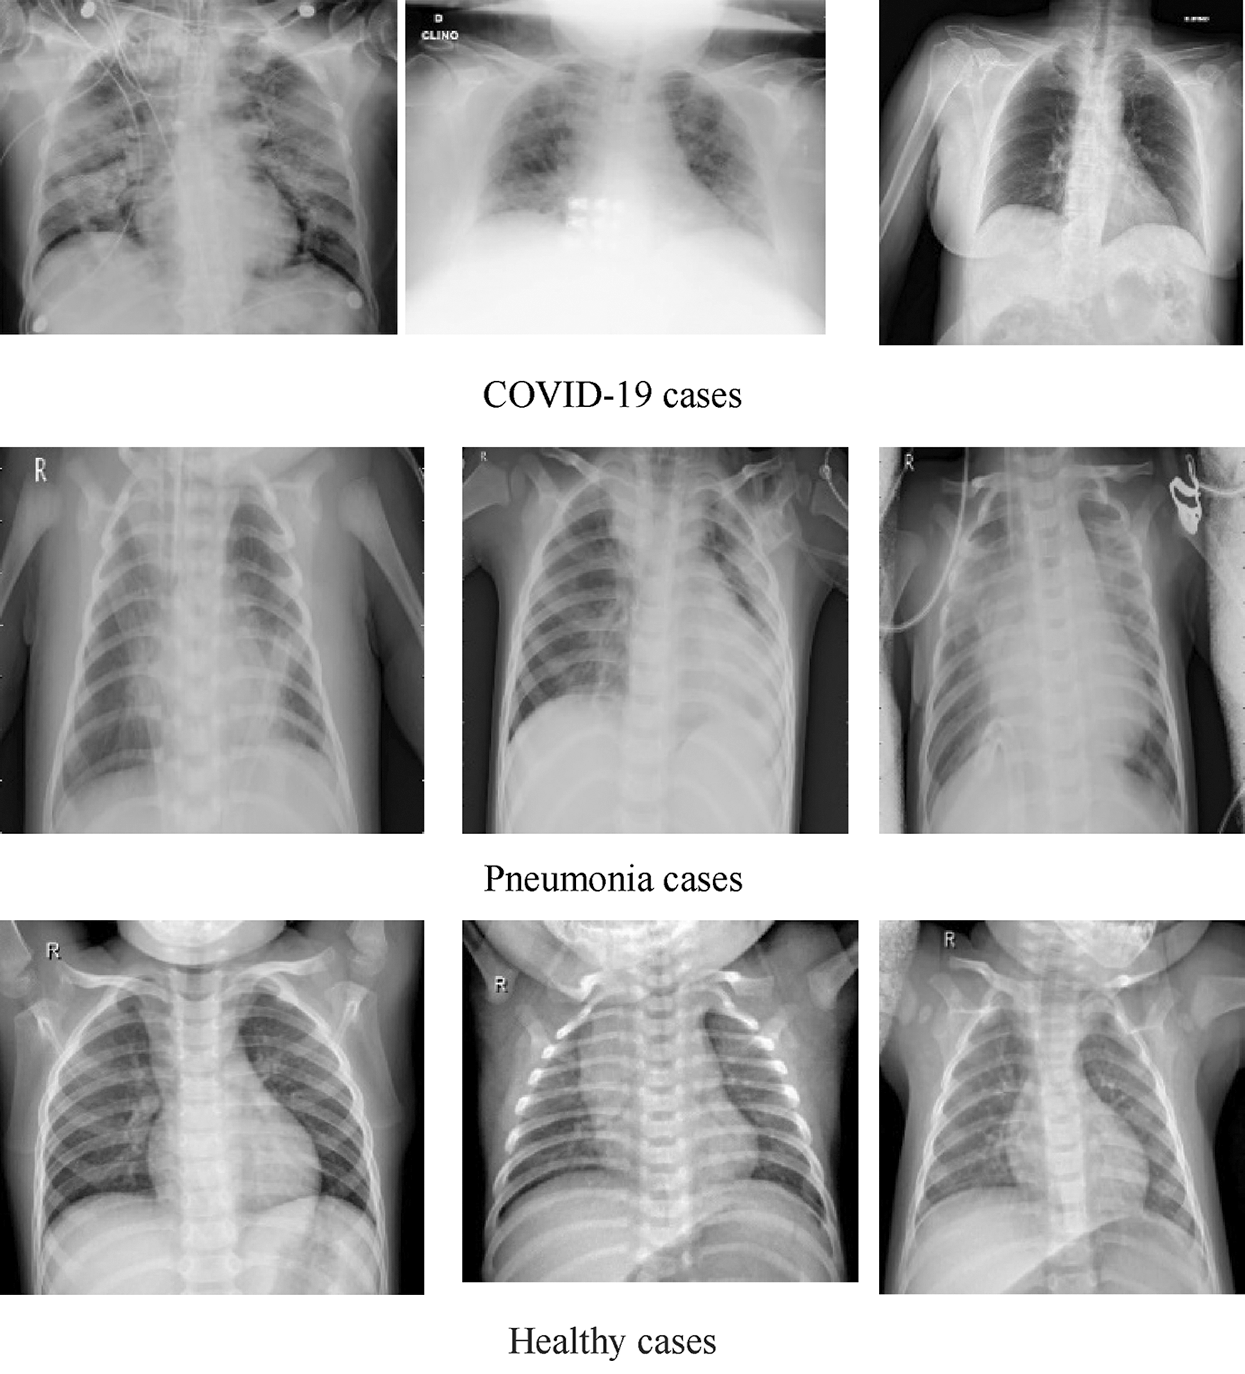

DATASET-2 [23] comprises three subdatasets. For the first subdataset, GitHub was explored for similar datasets. The authors took a set of X-ray images from Cohen [36]. For the second subdataset, the North American Radiological Society, Radiopaedia, and SIRM were closely examined. These sets can be found online [37]. The third subdataset was complemented with a series of common X-ray bacterial-pneumonia scans to enable the CNNs to differentiate COVID-19 from common pneumonia. Kermany et al. [38] made this collection available on the Internet. A total of 700 identified severe pneumonia images, 224 identified COVID-19 images, and 504 healthy condition images were included in DATASET-2 [23]. Fig. 2 illustrates some samples of DATASET-2.

Figure 2: Sample X-ray image from DATASET-2 shows COVID-19, viral pneumonia, and healthy cases